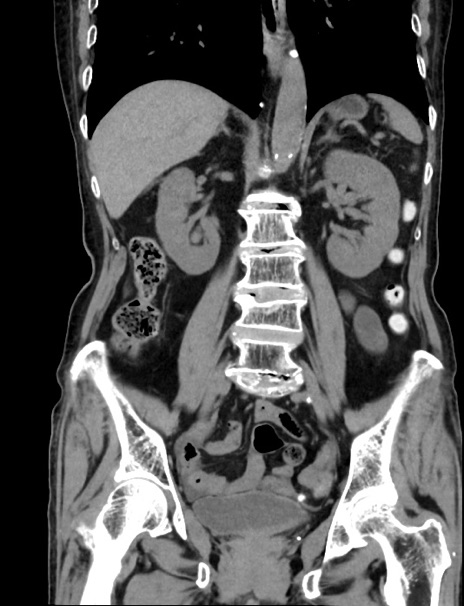

症例33(冠状断像)

【症例】70歳代 女性

【主訴】心窩部痛

【現病歴】延髄病変の精査・加療にて神経内科入院中。本日より心窩部痛あり。

【身体所見】右下腹部を中心に圧痛と反跳痛あり。

【データ】WBC 10900、CRP 0.02